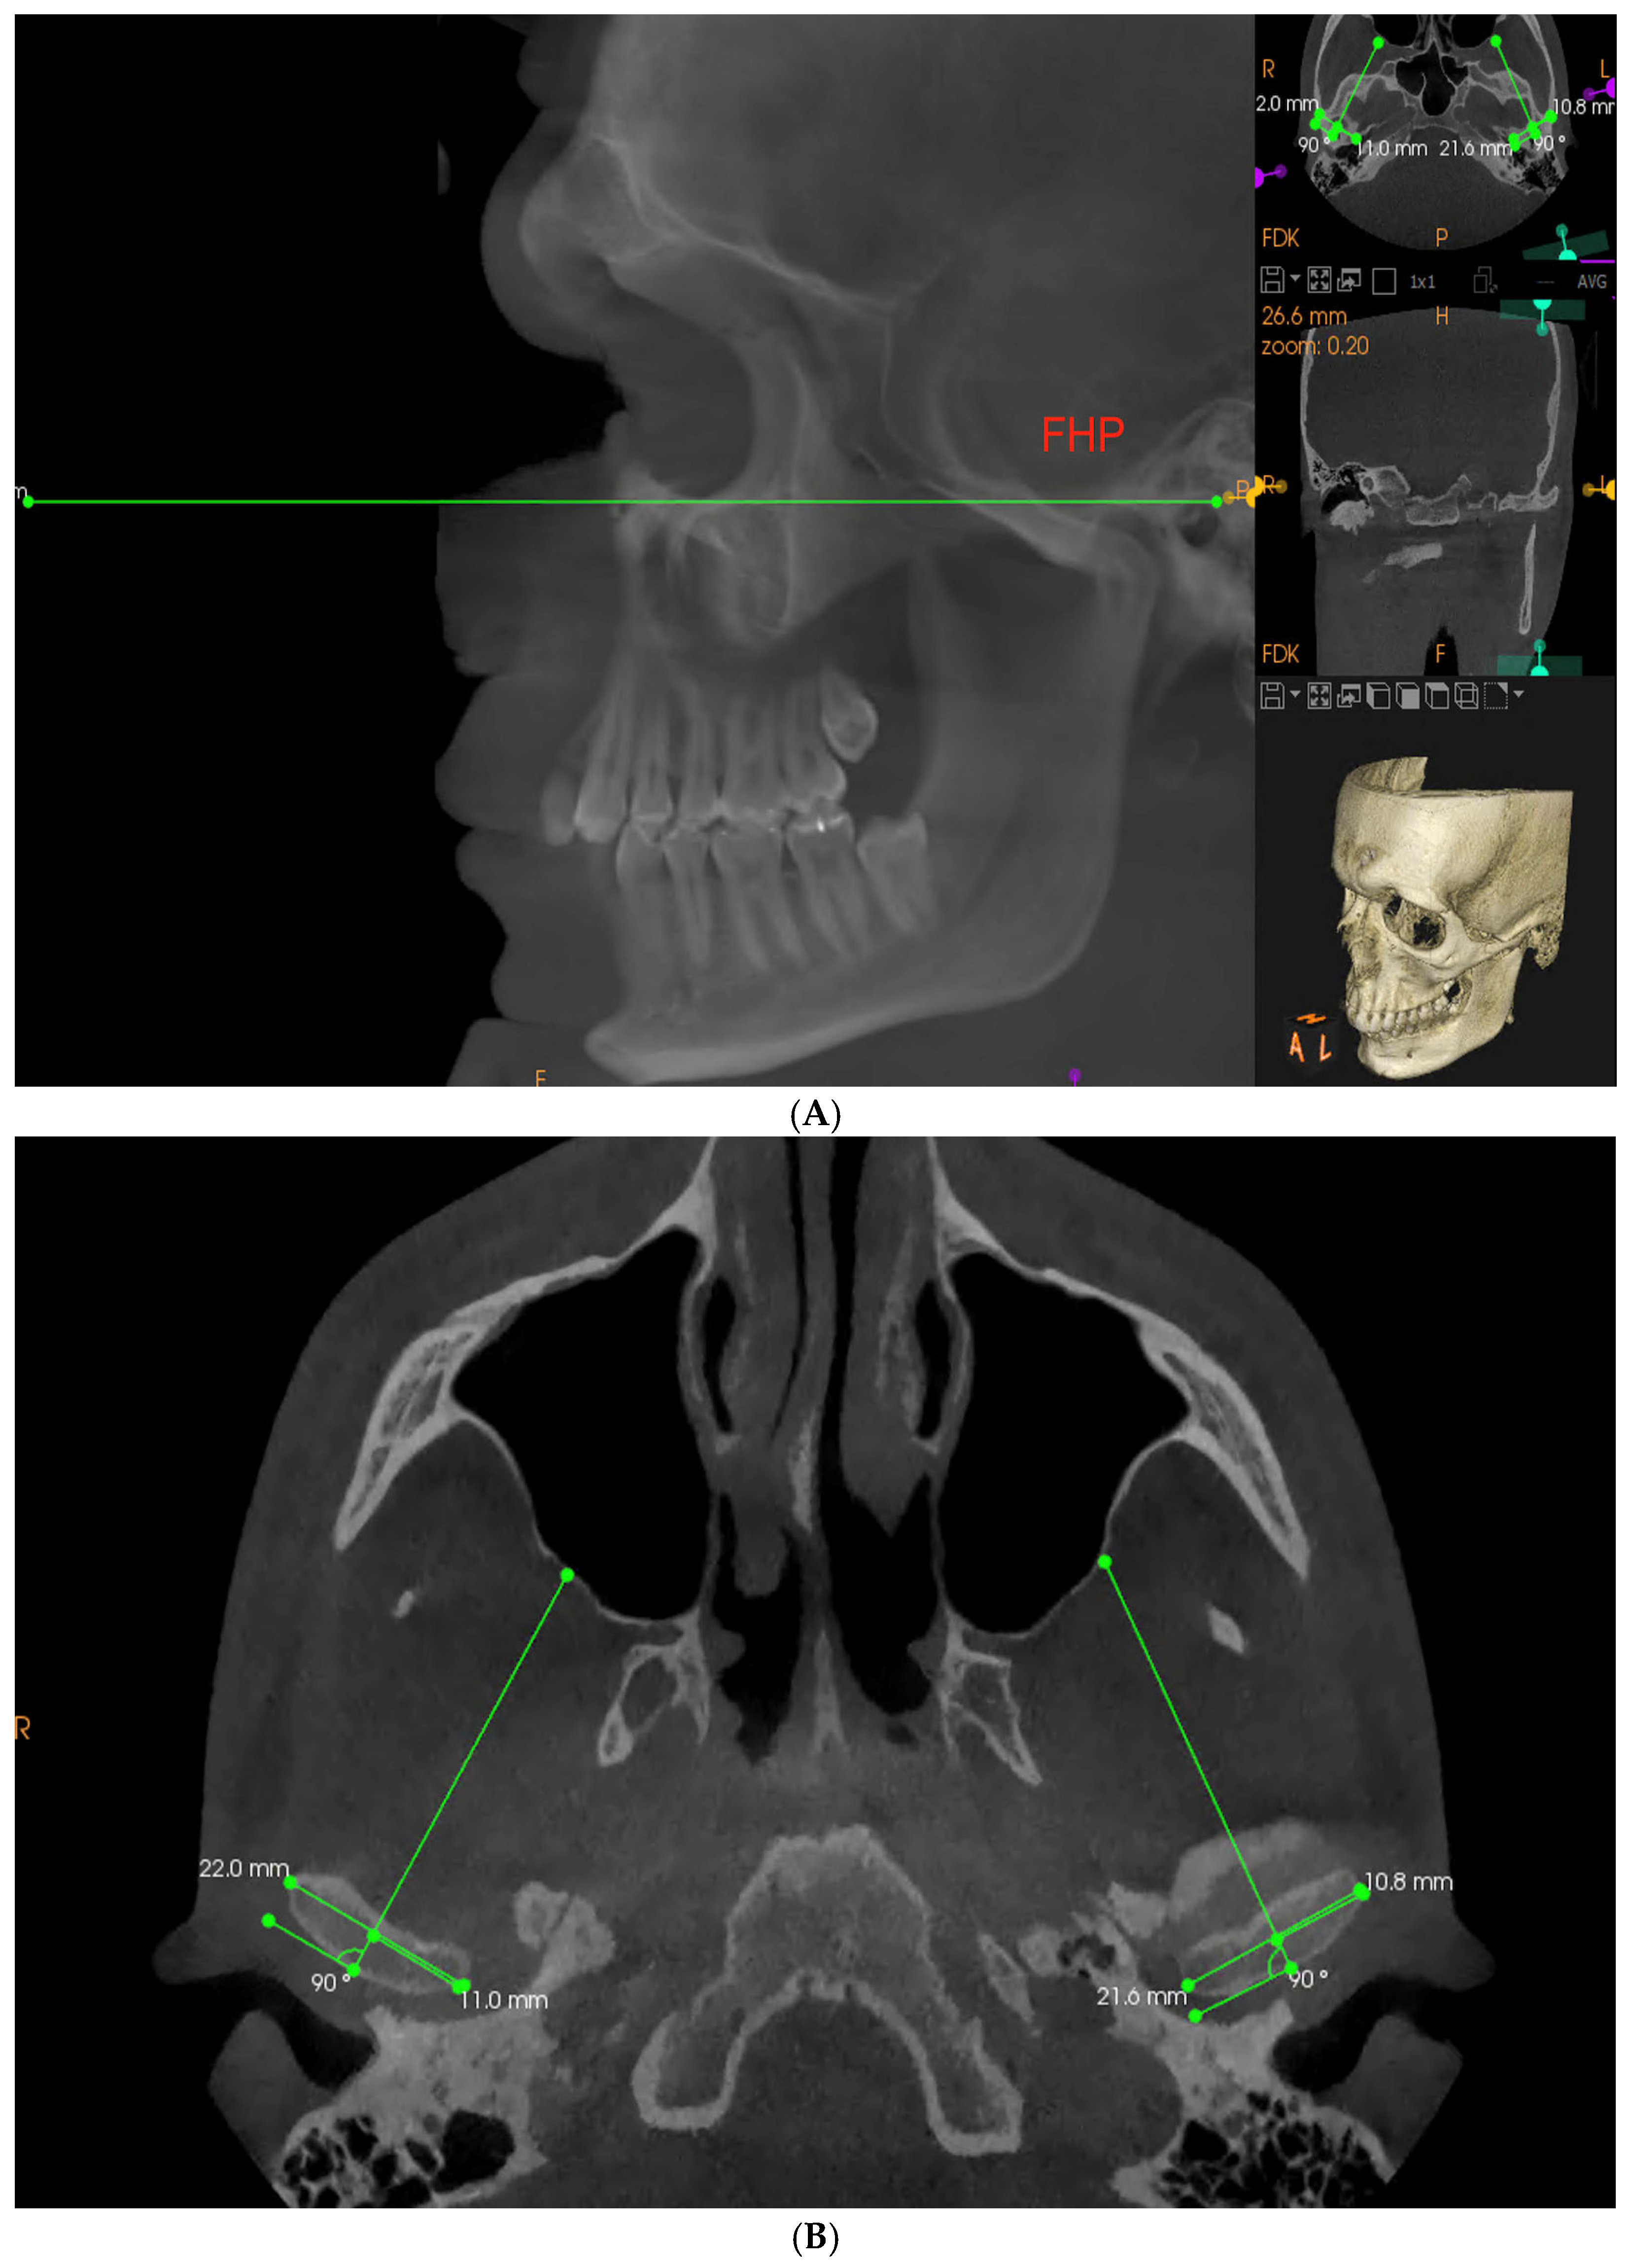

Each CBCT examination was conducted by an experienced radiologist technician with the use of Carestream 9300 device (Carestream Dental, Altanta, GA, USA), set to following parameters: 120 kV, 3.20 mA, 40 s with 1698.19 mGy/cm2 delivered. The patient was in standing position with the mandible in the maximum intercuspation position (MIP). Obtained images were analyzed in CS Imaging 8.0.5 program. To measure the SCGA on the obtained imaging examination, the Frankfort horizontal plane (FHP) was marked as a horizontal reference plane. It was constructed by connecting the left Orbitale and Porion points on both sides (Figure 1A) [28]. Next, in the sagittal view, a layer perpendicular to one running through the innermost and outermost point of the condyle in transverse cross-section was selected for each joint separately (Figure 1B).

Figure 1.

(A,B) Establishing a Frankfort reference plane and a proper CBCT layer to obtain reproducible measurements for all the patients according to anatomical landmarks (FHP—Frankfort horizontal plane).